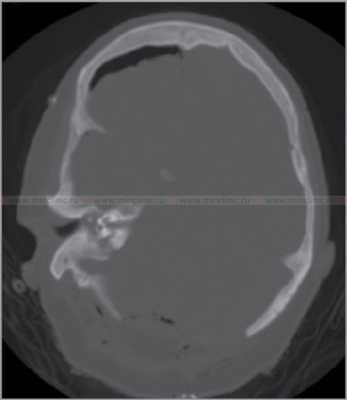

Аксиальная компьютерная томография (КТ) головы. Компьютерная томография (КТ) височной кости выявляет повреждение среднего уха, сосцевидного отростка и подлабиринтного пространства.